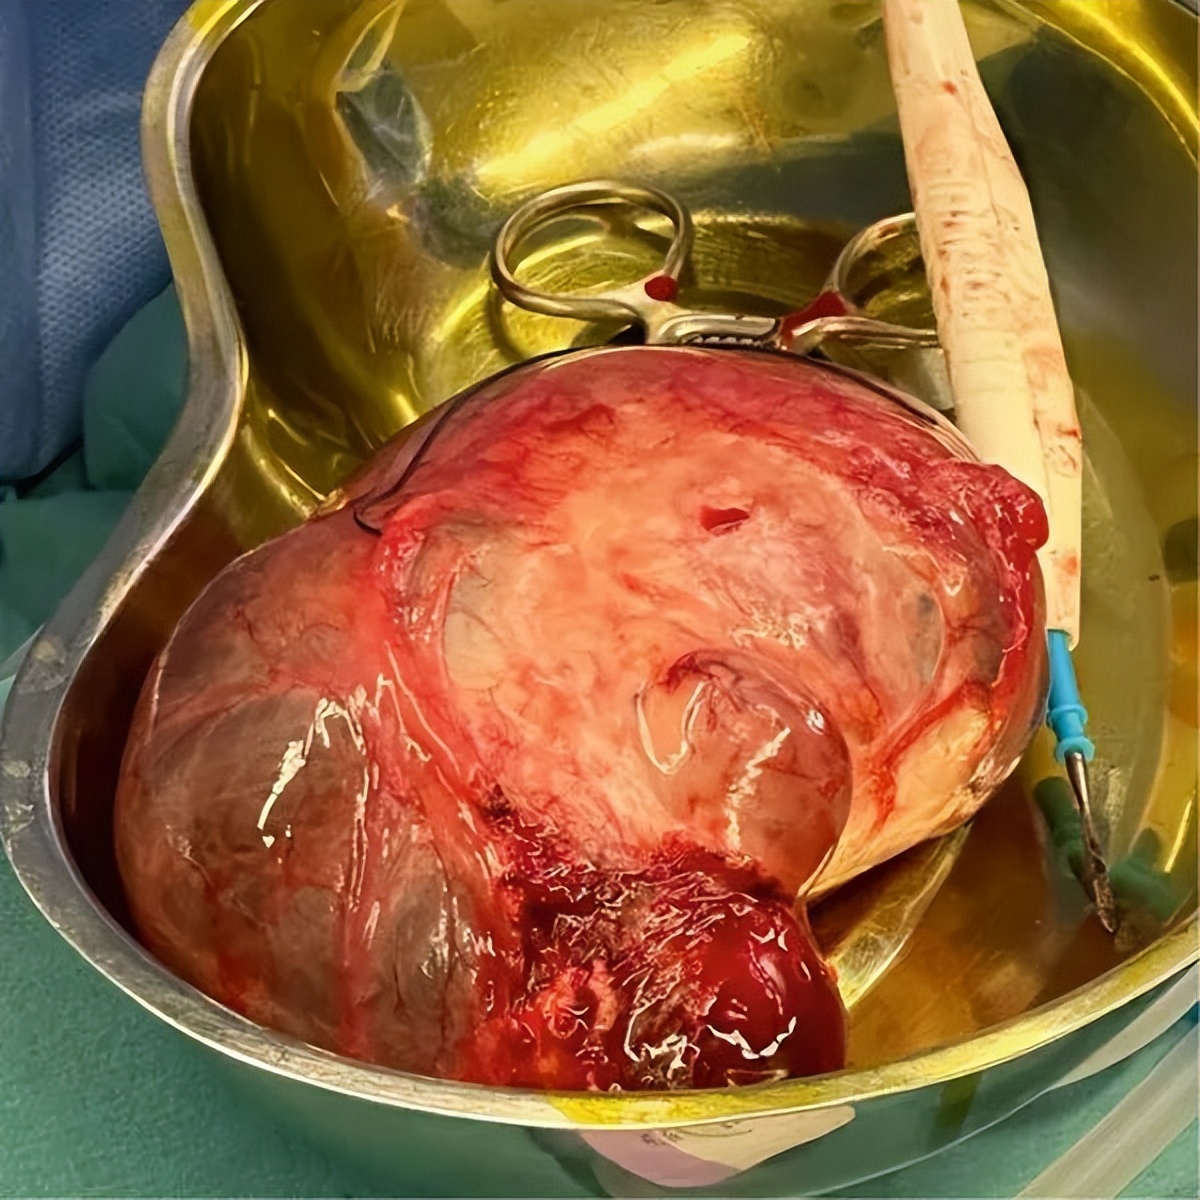

鉴于患者处于绝经前状态且MRI显示为典型的良性影像学特征,术前检查未包括血清肿瘤标志物(如CA-125),因为在良性病变中这些标志物可能非特异性升高,且对临床决策并非必需。在全身麻醉下,为患者实施了右侧输卵管卵巢切除术(图3)。卵巢囊肿移除后,结扎了骨盆漏斗韧带。图4显示卵巢蒂被切断并缝合,过程顺利,无粘连或其他问题。

图3.术中照片显示一个较大的卵巢囊肿

图4.术中照片显示卵巢囊肿切除术中的较大卵巢囊肿

术后患者恢复良好,未出现任何并发症。组织病理学分析显示,囊肿壁结构曲折,由黄素化的颗粒细胞构成,伴内层纤维组织层和外层卵泡膜细胞层。附着的输卵管外观正常,组织中可见白体。所检切片未见恶性肿瘤迹象,这为患者未来的健康提供了希望。完整囊肿测量为15×9 cm,囊壁光滑、菲薄,内含清亮黄色液体,可见被拉长的输卵管,长10厘米。代表性切片分装在三个标本盒中送检。安排患者在术后1个月和3个月进行随访。两次随访中,患者均表示既往症状已完全消失。